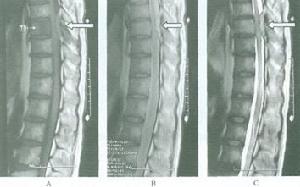

磁共振對脊髓及其椎管病變特別敏感,首先能準確定位並對受累節段的脊髓、椎體、椎板、椎間孔等結構能明確分辨,因受腫瘤壓迫鄰近脊髓水腫或受壓變形,常為高T1及高T2信號。注藥增強檢查後,往往發現病變能明顯強化。總之,通過磁共振檢查能夠準確發現椎管內轉移瘤的位置、腫瘤本身特徵,鄰近脊髓與神經根的受壓情況,為進一步治療提供最準確的信息。